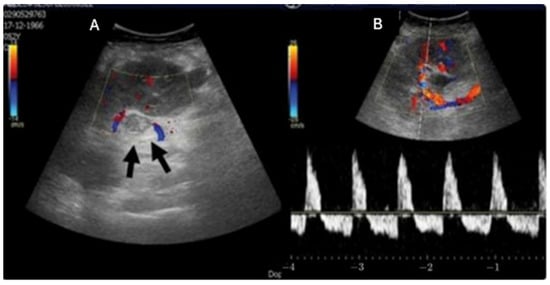

Advances in Noninvasive Imaging for Hypertensive Kidney Disease: Ultrasound and Elastography Insights

Hypertensive kidney disease (HKD) represents a significant contributor to chronic kidney disease and end-stage renal failure, yet its early detection remains challenging due to nonspecific clinical and imaging findings. The lack of a noninvasive diagnostic tool, preventing the use of biopsy and diagnosis by exclusion, suggests the underdiagnosis of patients and overestimation of HKD as the cause of renal replacement therapy. Ultrasonography, including Doppler assessment and renal resistive index measurements, provides a widely accessible, noninvasive approach to evaluate renal structure and hemodynamics, aiding in the identification of early renal impairment or renal artery stenosis. Shear-wave elastography (SWE) has emerged as a promising modality for noninvasive assessment of renal stiffness, potentially detecting structural changes prior to functional deterioration. Current evidence demonstrates SWE’s diagnostic potential in chronic kidney disease and early hypertensive renal disease; however, limitations such as inter-device variability, heterogeneous patient populations, and short follow-up periods constrain its clinical applicability. Neither ultrasonography nor SWE can yet serve as standalone diagnostic tools for HKD, emphasizing the need for standardization, further validation, and longitudinal studies to clarify their role in patient management and prediction. Full article

Show Figures

Figure 1